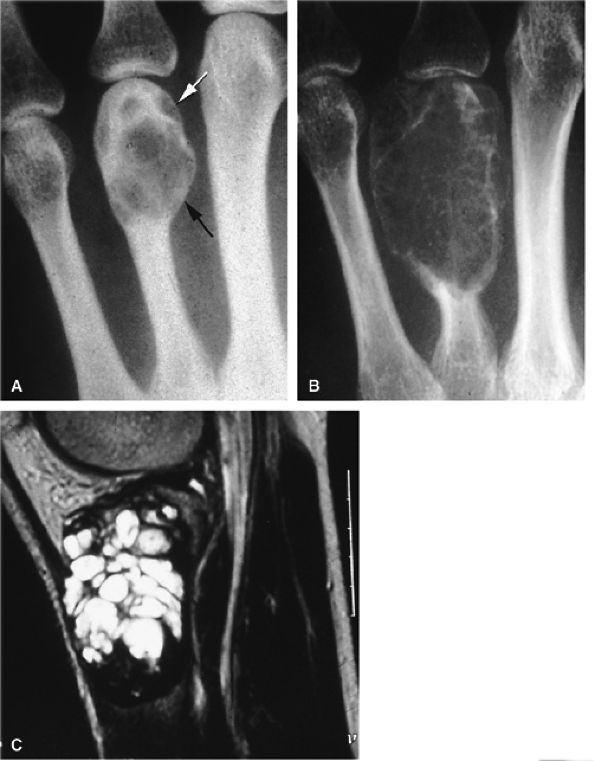

FIGURE 11.100 ● Giant cell tumor of the metacarpal. (A) Oblique view radiograph showing an expansile osteolytic lesion (arrows) of the distal metaphysoepiphysis of the fourth metacarpal. (B) One year later, there is an increase of expansion, cortex osteolysis, and numerous intralesional septa. (C) Sagittal T2-weighted image of the right knee shows the appearance of an identical lesion in the superior tibia.

FIGURE 11.89 ● Enchondroma of the proximal phalanx. Sagittal T2-weighted (A) and T1-weighted (B) images. Sagittal (C) and axial (D) fat-suppressed T1-weighted images after gadolinium administration. A centromedullary expansile lesion with cortical thinning and scalloping (arrows) can be seen. There is high signal on the T2-weighted image and lobulated peripheral enhancement.

|